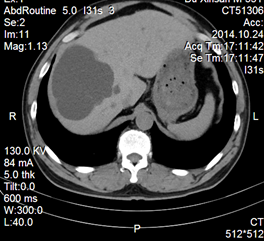

肝、肾囊肿是常见疾病,药物治疗基本无效,外科手术创伤大,费用高,并发症高,在影像学引导下穿刺引流及硬化治疗现在已为首选治疗。

典型病例、患者、男、55岁,因发现巨大肝囊肿,在我院介入科行CT引导下穿刺引流+硬化治疗术后恢复良好。